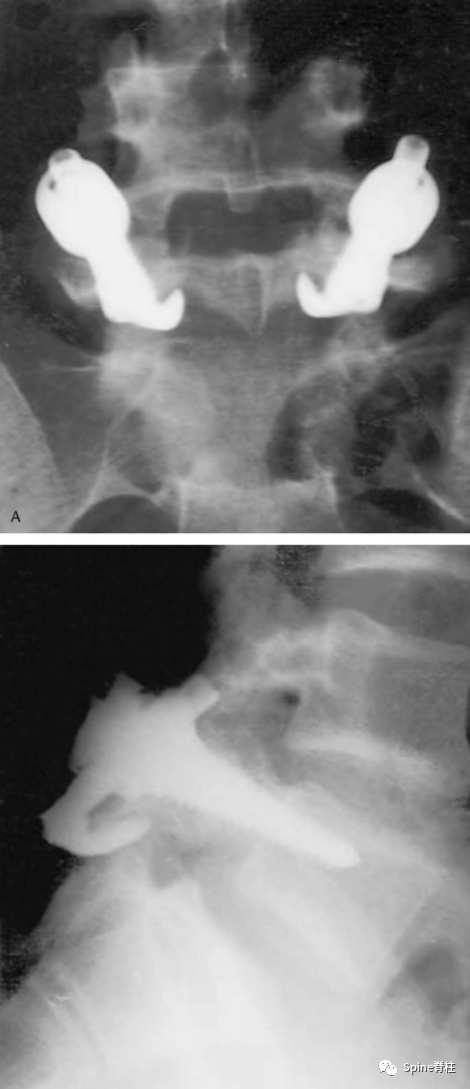

诊断腰椎峡部裂,腰椎双斜位片通常是需要的,表现为“苏格兰狗脖子”断了(见下图)。但对于一些隐匿的患者,腰椎双斜位片是看不出的,这时候需要行腰椎CT、MRI进一步明确诊断,少数部分需行核素骨扫描才能明确诊断。

1. 腰椎峡部和峡部裂在X线斜位片的表现

腰椎峡部在腰椎斜位片上常比喻为苏格兰狗(Scotty dog)的脖子

椎弓崩裂征象:X线腰椎45°斜位摄片示上关节突轮廓似"狗耳",横突似“狗头/嘴”,椎弓根似“狗眼”,下关节突似“狗前肢”,关节突肩部或称峡部似“狗颈部”。椎弓峡部崩裂时,“狗颈部”可见裂隙。

腰椎斜位片上的苏格兰狗和断裂的脖子(峡部裂)